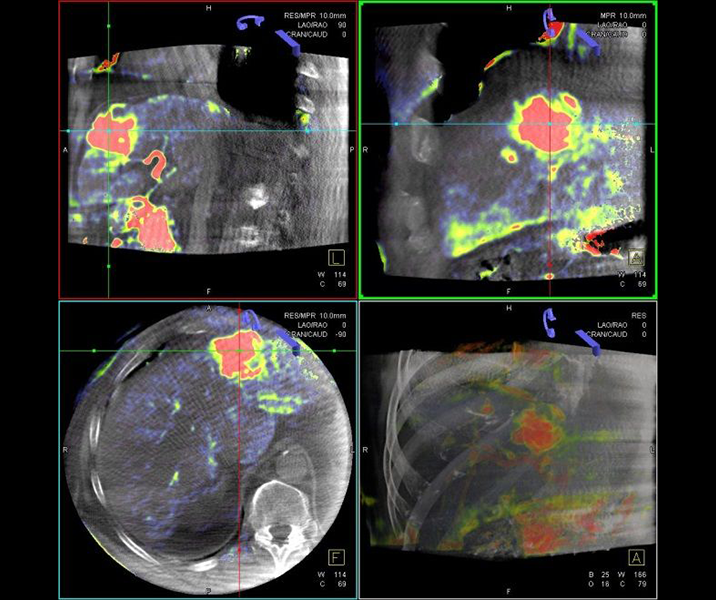

Selektive Interne Radio-Therapie (SIRT)

Die Selektive Interne Radiotherapie (SIRT) wird in der Fachliteratur auch Radioembolisation (RE) genannt. Hierbei werden gezielt kleine, radioaktive Kügelchen, sog. Mikrosphären, über den Katheter (siehe TACE) von mehreren Positionen in der Leber mit dem Blutstrom in das gut durchblutete Tumorgewebe gebracht und bleiben dort in den kleinen Gefäßen "stecken", die den Tumor ernähren. Von dort bestrahlt das in den Kügelchen enthaltene radioaktive Element Yttrium-90 über mehrere Tage hinweg das Tumorgewebe und zerstört es selektiv. Dieses Verfahren kann bei Leberkrebs oder -metastasen eingesetzt werden, wenn die Herde trotz Chemotherapie weiter wachsen und nicht chirurgisch oder mittels RFA und TACE behandelbar sind.

Das Verfahren wird von der interventionellen Radiologie zusammen mit der Partnerabteilung der Nuklearmedizin sowie den entsprechenden Partnerkliniken geplant und durchgeführt.

Abbildung Körper: Schematische Darstellung des Zugangsweges bei SIRT-Therapie über die Leistenarterie. Die arteriellen tumorversorgenden Gefäße in der Leber werden selektiv dargestellt und von dort wird die Therapie lokal appliziert. (Bildrechte beim Thieme-Verlag!)